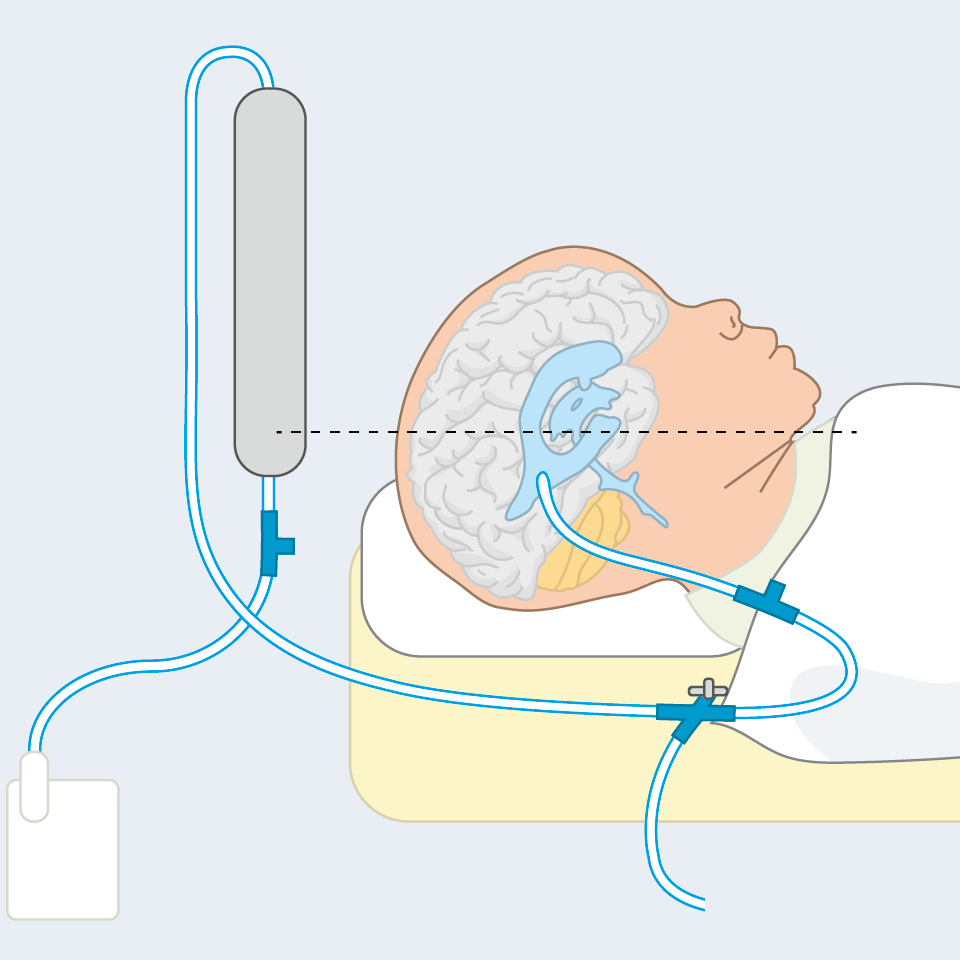

Herzlich willkommen! Ich bin Ihre Expertin für medizinische Illustrationen und kreative Kinderbuch-Illustrationen. Mit einem Auge für wissenschaftliche Genauigkeit und einer Liebe zur Gestaltung kindgerechter Erzählwelten schaffe ich Bilder, die informieren und begeistern. Entdecken Sie mein Portfolio und lassen Sie sich von meiner Arbeit überzeugen!